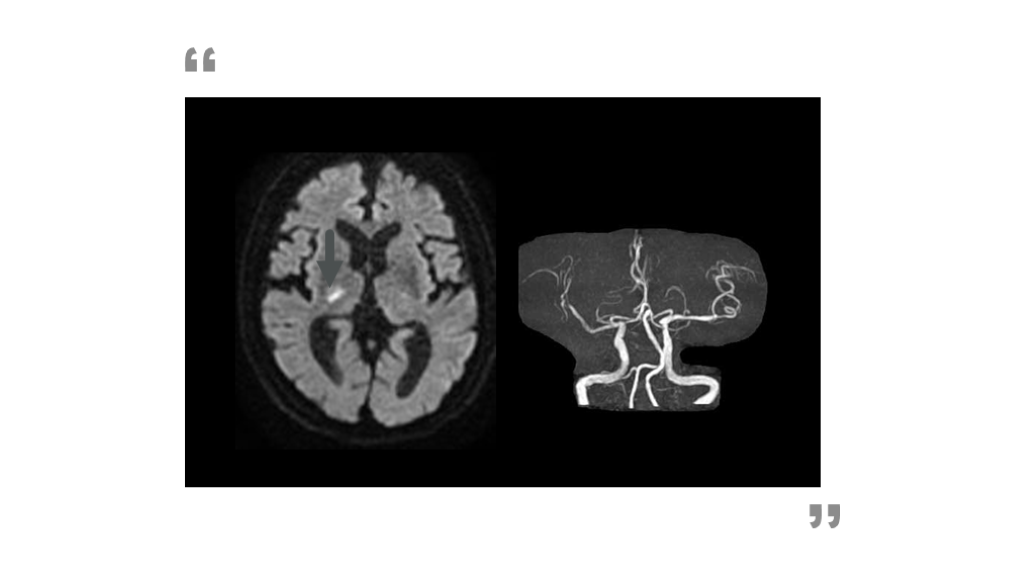

アテローム血栓性脳梗塞の発症機序

主幹動脈狭窄が原因で、それより遠位の血流領域に虚血を来しうる。

定義:「虚血病巣を還流する血管に 50%以上の狭窄がある」